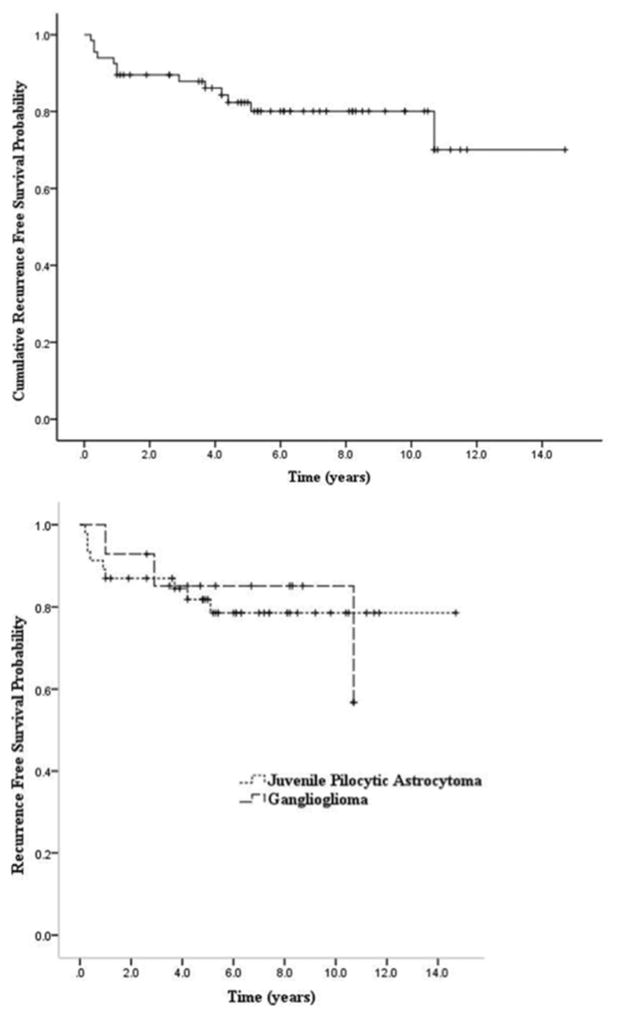

Kaplan-Meier curves were plotted for the cumulative recurrence-free survival following GTR for the overall population of 67 patients (Fig. 1 upper) and recurrence-free survival for patients with individual histopathological tumor types (Fig. 1 lower). Our data set contained only 6 DNETs and 1 glioneuronal tumor. Given the limited numbers, these 2 tumor types were not plotted as specific tumor types. The recurrence-free survival at 2 and 5 years after GTR for all low-grade glial and glioneuronal tumors was 0.90 (95% CI 0.82–0.97) and 0.82 (95% CI 0.73–0.92) respectively. For JPAs, the estimated 2- and 5-year recurrence-free survival was 0.87 (95% CI 0.77–0.97) and 0.82 (95% CI 0.7–0.93), respectively. Finally, using the limited data sets for ganglioglioma and DNET, the recurrence-free survival at 2 years was 0.93 (95% CI 0.79–1.00) and 1.00 and at 5 years was 0.85 (95% CI 0.66–1.00) and 0.67 (95% CI 0.12–1.00), respectively.

Fig. 1.

Kaplan-Meier estimates of cumulative recurrence-free survival of all study patients (upper) and patients with JPAs and gangliogliomas (lower).